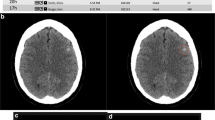

Advances in the field of artificial intelligence (AI), and in computing in the past decade, have made possible artificial neural networks that can “learn” to perform tasks previously reserved exclusively for humans. AI-enabled applications are already being deployed in radiology to assist in the detection and classification of diseases. The emergency department (ED), where timely and accurate diagnosis is critical, is an area of great interest for application of AI-driven solutions. AI algorithms offer great promise for addressing the challenges posed by increasing imaging volumes, increasing case complexity, and the need for rapid turnaround of results. Many products have already received US FDA clearance for clinical use. This chapter provides an introduction to key AI concepts, explores applications of AI in emergency radiology, and considers implications that AI will have for the field.